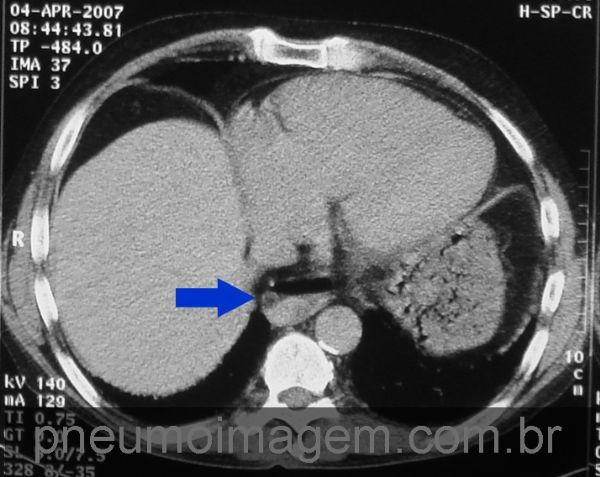

Esclerose sistêmica progressiva (esclerodermia). Redução do volume de ambos os pulmões devido às opacidades intersticiais com faveolamento pulmonar.

Observe a dilatação do esôfago (seta vermelha). Chaves: scleroderma; esophageal dilation.

Dilatação do esôfago com nível hidraéreo (seta azul).

Chave: nível líquido.